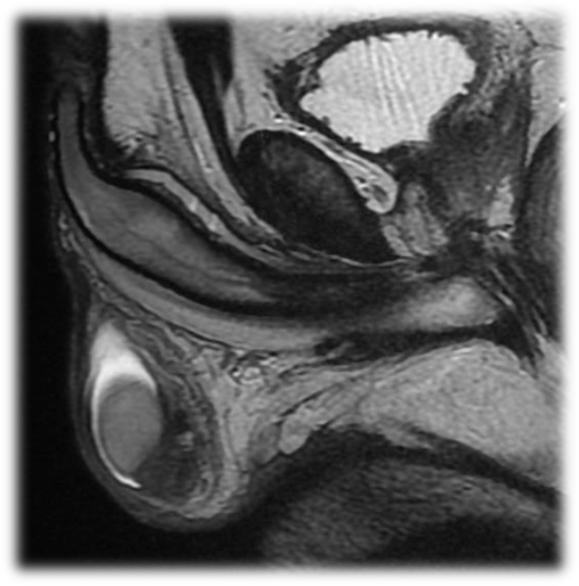

• Encaminhado por aumento do volume testicular e dor em região escrotal à direita há 3 meses

• Presença de nódulo endurecido na região inferior abaixo do testículo direito, porém, sem plano de clivagem à palpação

Características de imagem sugestivas de TB

• Aumento heterogêneo do epidídimo (principalmente cauda) associado a lesão testicular;

• Calcificação da túnica albugínea;

• Acometimento concomitante de outras estruturas do trato urogenital.